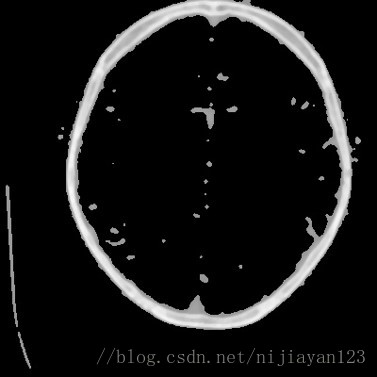

在进行剪切以后,由于进行医学图像中有大量不必要的信息量,所以在这里我还进行了二值化操作。

可以看到在进行二值化操作之后和ground true对比可以发现,大部分细节还是保持了。这样有利于进行后面进行卷积操作。